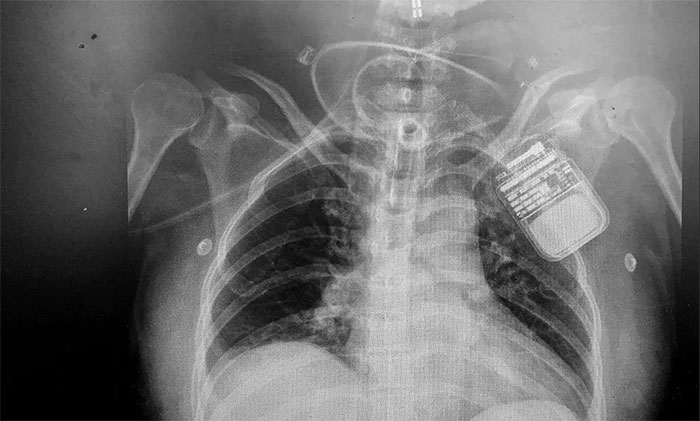

脊髓神经电刺激术是通过微创手术将电极置入脊髓上方,以脉冲电流刺激脊髓神经,增加脑血流、脑代谢,而且还能激活脑干网状上行系统,这样不仅能改善脑循环、缩小缺血灶,还能兴奋大脑皮层,促进患者神志清醒。

该技术具有微创、可逆,并可依据患者病情需要进行治疗参数的调节,实现个体化定制,同时可有效改善患者全身循环水平等优势,帮助对长期昏迷特别是“植物人”促醒。

▲ 电刺激器顺利置入患者脊髓上方